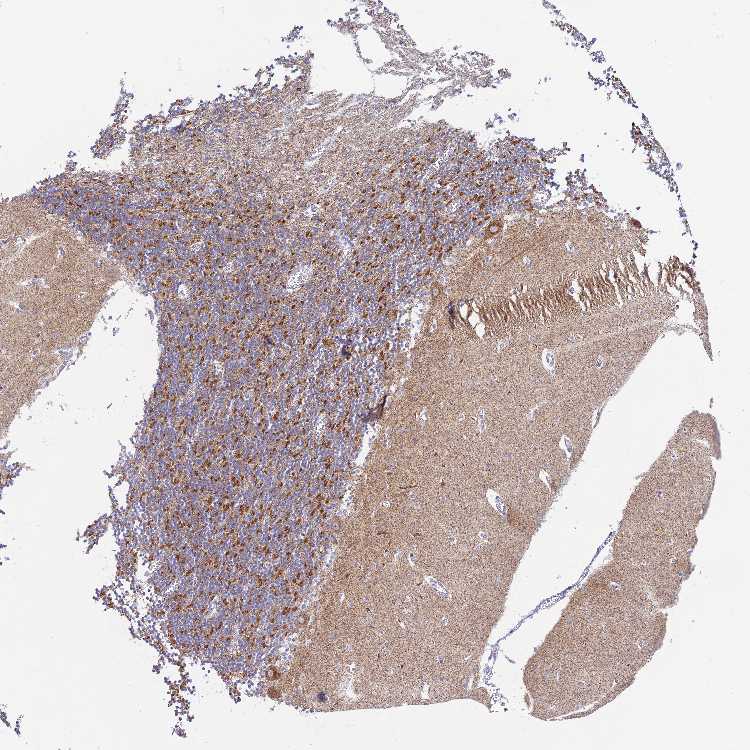

CEREBELLUM - Antibody stainingi

Antibody staining in the annotated cell types in the current human tissue is reported as not detected, low, medium, or high, based on conventional immunohistochemistry profiling in selected tissues. This score is based on the combination of the staining intensity and fraction of stained cells.

Each image is clickable and will lead to virtual microscopy that enables deeper exploration of all samples and also displays staining intensity scores, fraction scores and subcellular localization as well as patient and tissue information for each sample.

Antibody HPA046219

Purkinje cells High

Cells in granular layer High

Cells in molecular layer Not detected